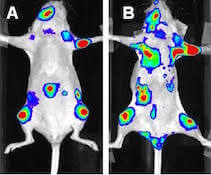

Wysoka czułość obrazowania w zakresie luminescencji oraz promieniowanie Cerenkova

Wysoka czułość obrazowania w zakresie luminescencji oraz promieniowanie Cerenkova

Aparat do przyżyciowego obrazowania zwierząt laboratoryjnych IVIS Lumina XRMS przeznaczony jest do badań dwuwymiarowych z zastosowaniem obrazowania luminescencyjnego, fluorescencyjnego oraz obrazowania promieniowania Cerenkova, a także RTG. Umożliwia to uzyskiwanie złożonych obrazów sygnałów fluorescencyjnych lub /i luminescencyjnych w kontekście obrazu RTG budowy anatomiczne zwierzęcia. Zaawansowana optyka, duży wybór filtrów wzbudzeniowych i emisyjnych, technologia Spectral Unmixing oraz wyposażenie dodatkowe takie jak dedykowany system anestezji gwarantują szerokie spektrum zastosowań aparatów IVIS Lumina XMRS zarówno w badaniach nad nowymi lekami, komórkami macierzystymi, rozwojem stanu zapalnego jak i w badaniach nad terapiami spersonalizowanymi. Standaryzacje badań gwarantuje możliwość absolutnej kalibracji zgodnej ze standardami NIST.